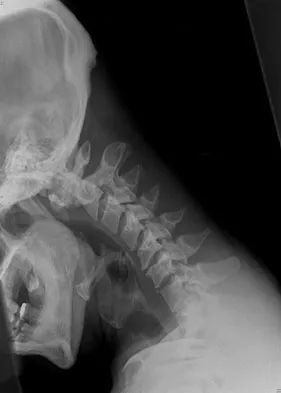

A 29-year-old man reports a 2-week history of severe neck pain after being struck sharply on the back of the head and neck while moving a refrigerator down a flight of stairs. Initial evaluation in the emergency department revealed no obvious fracture and he was discharged in a soft collar. Neurologic examination is within normal limits, and radiographs taken in the office are shown in Figures 21a through 21c. Subsequent MRI scans show intra-substance rupture of the transverse atlantal ligament. What is the most appropriate treatment option at this time?

Dickman and associates classified injuries of the transverse atlantal ligament into two categories. Type I injuries are disruptions through the substance of the ligament itself. Type II injuries render the transverse ligament physiologically incompetent through fractures and avulsions involving the tubercle of insertion of the transverse ligament on the C1 lateral mass. Type I injuries are incapable of healing without supplemental internal fixation. Type II injuries can be treated with a rigid cervical orthosis with a success rate of 74%. Surgery may be required for type II injures that fail to heal with 3 to 4 months of nonsurgical management. Findlay JM: Injuries involving the transverse atlantal ligament: Classification and treatment guidelines based upon experience with 39 injuries. Neurosurgery 1996;39:210.